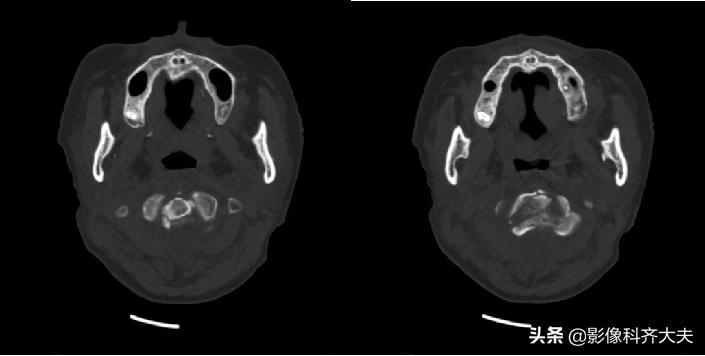

枢椎骨折

枢椎骨折矢状面重建